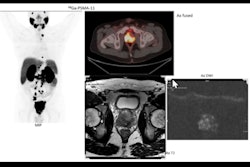

This interactive three-day online fellowship will take participants through staging and restaging rectal cancer on MRI. Following a series of lectures followed by case readings and discussions.